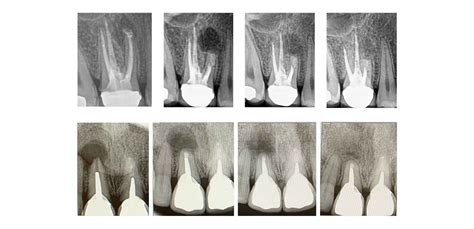

De forma previa a la apicectomía, se realiza al paciente una exploración con una radiografía CBCT para obtener la información necesaria y planificar el caso adecuadamente.

El objetivo de la cirugía periapical es extirpar la lesión periapical, aislar los conductos radiculares con un sellado eficaz y evitar la recidiva de la infección. De esta manera, mediante esta intervención se consigue una obturación adecuada del ápice del diente, evitando que se mantenga la inflamación y la infección de los tejidos.

La cirugía endodóntica cuenta de tres técnicas básicas que son: el legrado apical, la apicectomía y la obturación retrógrada.

La definición clínica de éxito es la de una pieza dental sin síntomas mientras que la definición de éxito radiológica es la de la resolución de la radio-lucidez periapical.